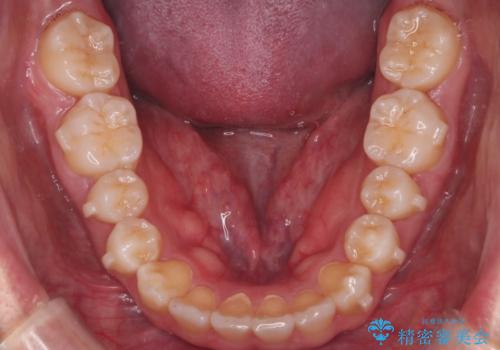

上の前歯が出ているという主訴が綺麗に改善されました。

その他の部位のがたつき、奥歯の噛み合わせも以前と比べると良くなっています。

目立たない装置で治療期間も10ヶ月と短く終了することができました。